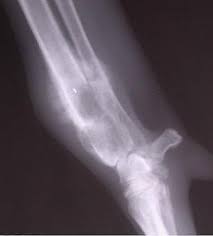

If your cat has an osteosarcoma of the limb (appendicular osteosarcoma), lameness or a distinct swelling may be noted.

This is one reason you want to ensure your cat has regular wellness visits to the veterinarian. Additionally, some dogs and cats with myeloma develop hypercalcemia, a higher than. Your cat may be more lethargic, have loss of appetite, and be reluctant to walk or play due to pain caused by the tumor on the bone. Osteosarcoma progresses rapidly, so early recognition of symptoms is essential to successful treatment. For the most part, mammary gland carcinoma is an incidental finding, meaning that during a veterinary checkup, lumps inside breast tissue are found. Acute lameness may be due to a bone fracture hard, obvious swelling over a long bone of a limb Symptoms of multiple myeloma in cats the major symptoms associated with multiple myeloma are caused by the spread of cancer cells, hyperviscosity syndrome (thick blood), and the underproduction of normal cells within the bone marrow (see explanations above). Notice if your cat also has difficulties or changes while urinating. Bone cancer in cat symptoms symptoms of bone cancer in cats can mimic those of arthritis, and include stiffness, limping, and pain. In some cases, cats suffering from bone cancer will appear tired or have anorexia. A lot of cat cancer symptoms can be illness or other diseases too. Tumors that occur in the back of the mouth or under/on the tongue are rarely seen until signs of drooling, weight loss, halitosis (bad breath), difficulty eating, and bloody discharge from the mouth are noted. There appears to be no predisposing cause of osteosarcoma.

Osteosarcoma In Cats Vca Animal Hospital from vcahospitals.com Bone cancer in cat symptoms symptoms of bone cancer in cats can mimic those of arthritis, and include stiffness, limping, and pain. Common tumor symptoms in cats to take care of any cancer before it worsens, regularly watch your feline for the following tumor symptoms: Externally we can see lumps and bumps. If your cat has an osteosarcoma of the limb (appendicular osteosarcoma), lameness or a distinct swelling may be noted. Mammary gland cat cancer symptoms. One of the most common symptoms of cat cancer are lumps and bumps. unusual lumps that change size could be a sign of cancer. But sometimes your cat may have a tumor that you can't feel from the outside. This is one reason you want to ensure your cat has regular wellness visits to the veterinarian.

Symptoms of multiple myeloma in cats the major symptoms associated with multiple myeloma are caused by the spread of cancer cells, hyperviscosity syndrome (thick blood), and the underproduction of normal cells within the bone marrow (see explanations above). The age range for cats with osteosarcoma is wide with rare cases less than a year, although the average age of cats with the tumors (10.5 years) is older than that of dogs. Bone cancer in cats (osteosarcoma) there are different types of bone cancer, but osteosarcoma is the most common. In some cases, cats suffering from bone cancer will appear tired or have anorexia. There appears to be no predisposing cause of osteosarcoma.

Sadly, one in five cats get cancer. What you should know about osteosarcoma (bone cancer) in cats. If you find unexplained lameness in your cat, then it's a very common sign of bone cancer. 12 warning signs of cancer in cats. Sadly, one in five cats get cancer. Also known as osteosarcoma, bone cancer is a common diagnosis in felines. Weight loss, even if your kitty seems to be eating the same amount as ever. For the most part, mammary gland carcinoma is an incidental finding, meaning that during a veterinary checkup, lumps inside breast tissue are found. A simple test by your vet will indicate the treatment protocol. If a veterinarian suspects a bone tumor, he or she may consult with a veterinary oncologist and/or surgical specialist. Cats are tricky because they hide disease well. A type of bone cancer called osteosarcoma is the most common type of primary bone cancer, accounting for over 95% of all bone tumors.other types of bone cancer are chondrosarcoma, fibrosarcoma, and hemangiosarcoma. Because of the rapid nature of the disease, it is important to seek treatment early.